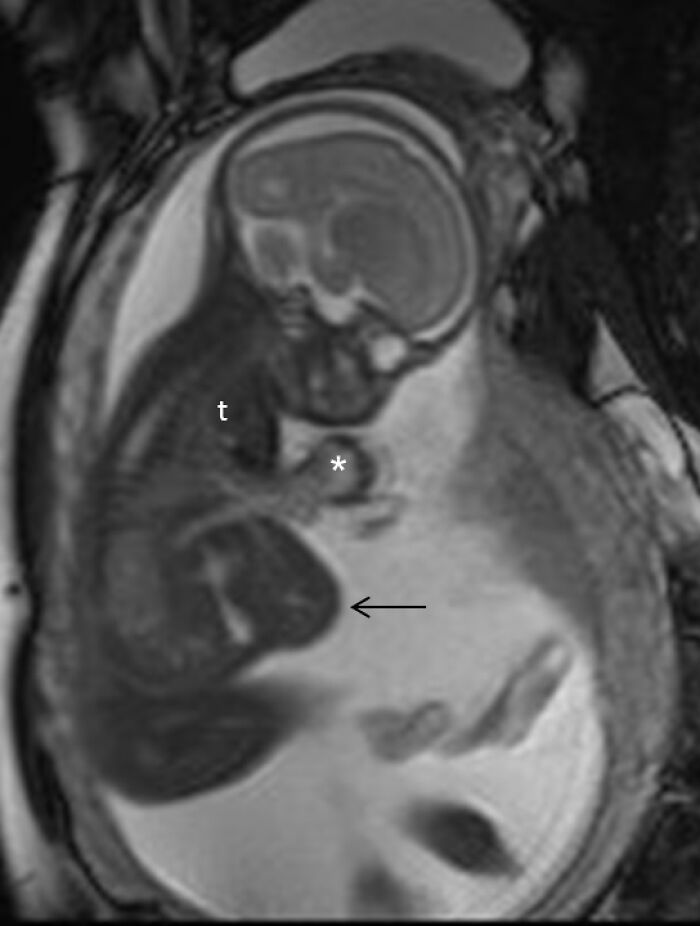

Fetus-in-fetu. 10 year old boy "pregnant" with his parasitic twin (PT).

Edit:

Case

10 y.o. boy came in with enlarging abdominal mass and intermittent generalized weakness. Imaging revealed a parasitic "fetus" which was also growing in size. History revealed mass noted 2 years ago which enlarged rapidly the last 3-4 months. Within days of admission, boy's organs begin to fail with no apparent reason. He was healthy and eating well when he was admitted. Family wanted surgical intervention to separate the parasitic twin against surgeons' advice. parasitic twin was basically starving/poisoning the boy. Surgeons opened the boy up and found that the boy and parasitic twin share a (stomach, liver, heart, blood vessels - mesodermal organs) basically too complex to operate. The boy passed away after.

This happened to a poor family in a underfunded government hospital in a corruption-infested country. The parasitic twin was donated to the hospital. It had teeth with hairy limbs with the longest curved baby nails. I can't describe it further. It is on display at the Surgeon's Hall.

Edit 2:This happened years ago before the age of smartphones.The hospital team tried to have the tissues studied for academic purposes. there was a case report about it presented in a local medical congress but as this happened in a "third world" country with limited resources, nothing came of it. I live and work in a different country now.

Image credits: xtranscendentx